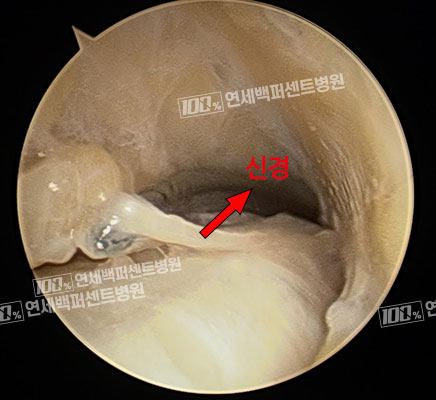

내시경 손목건초 유리술 전 : 내시경 소견

내시경 손목건초 유리술 후 : 내시경 소견

손목 힘줄에 끼여 있는

만성염증 조직

염증에 눌려있는 손목신경

내시경을 이용하여 긴 절개 없이, 손목건초염 치료!

염증으로 두꺼워진 힘줄막 복원 + 만성 염증 조직 변연 절제술 동시 시행으로 완치율 UP!